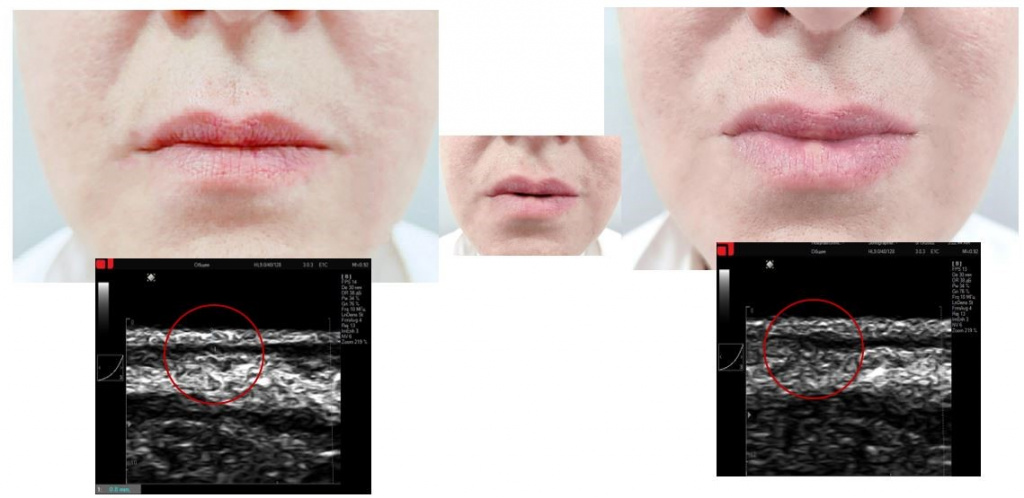

Протокол работы в зоне губ

Работа по протоколу «Lovely lips» предусматривает воздействие как с целью уменьшения объема, так и с целью его восполнения, а также устранения асимметричности их объема.

Протокол работы в зоне губ PicoCare

Рис. 6. Увеличение объема губ по протоколу «Lovely lips» (PicoCare)